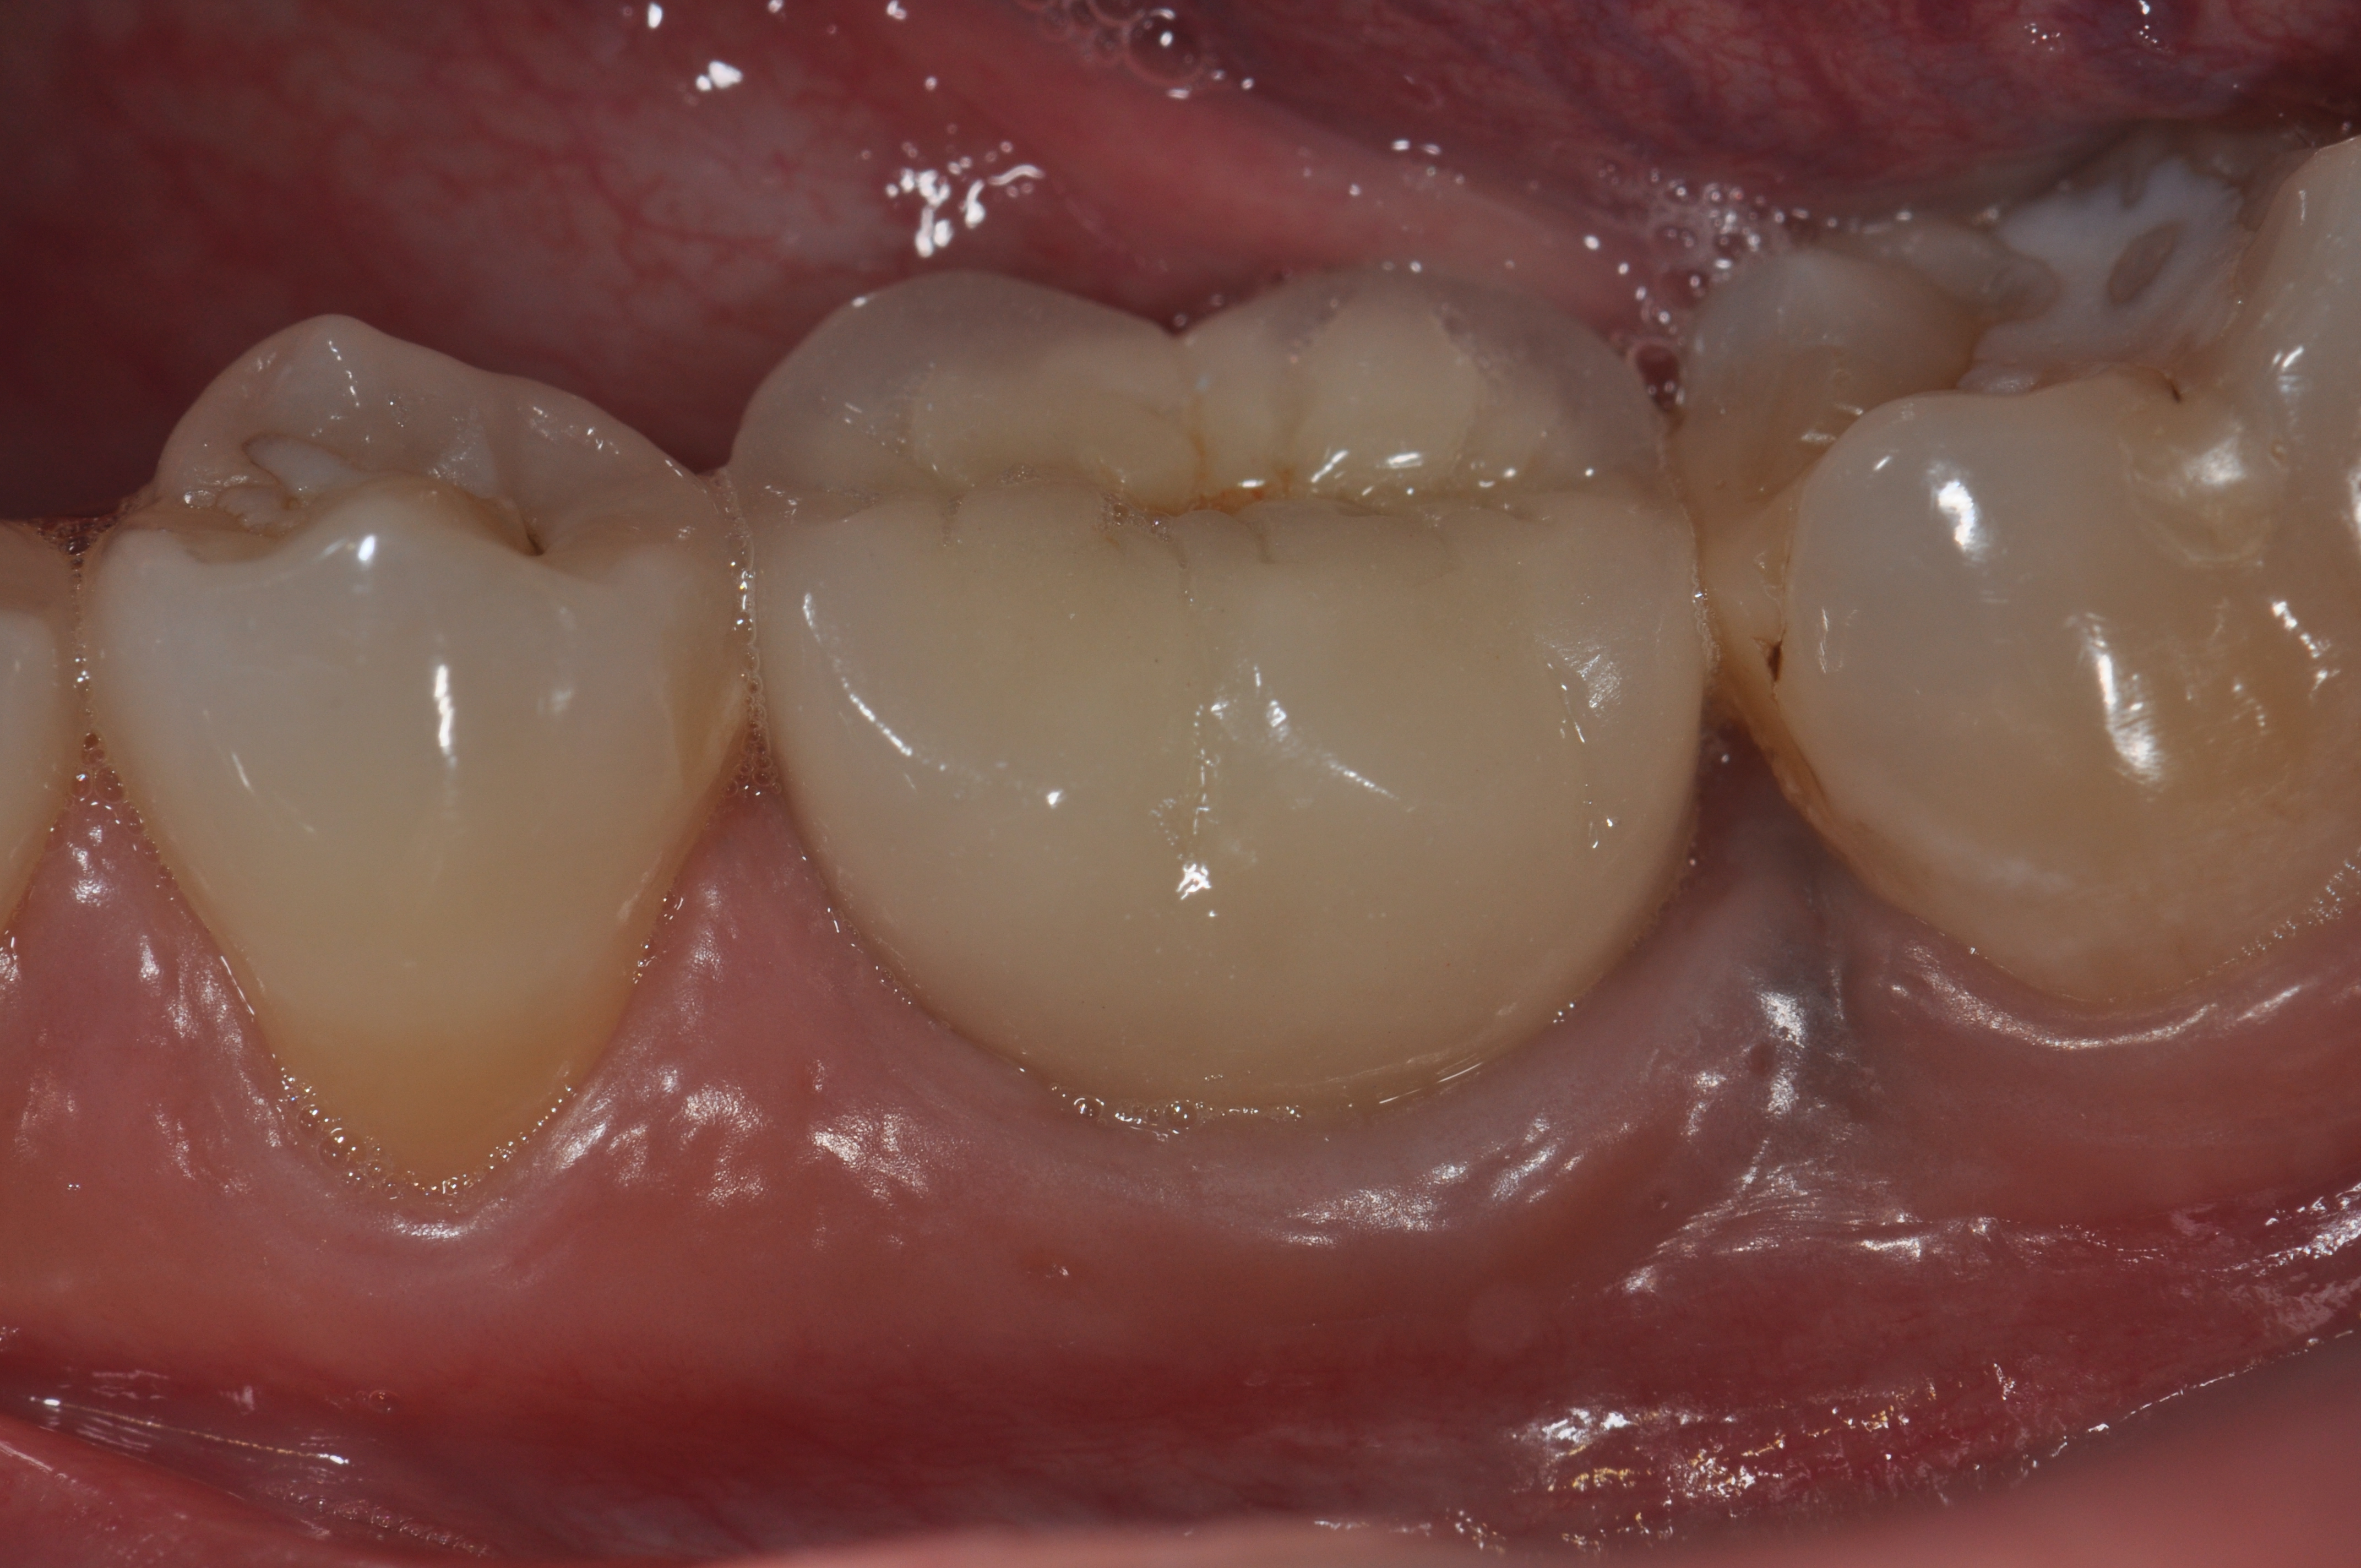

Fig 6. A clinical view of this area suggests that peri-implant mucositis is present. The tissue is swollen, it bleeds on probing, has 5 mm of probing depth, and exhibits purulent exudate.

Figure 6